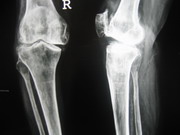

Knee Joints Case A

Knee Joint Replacement Knee Joint Replacement Knee Joint Replacement